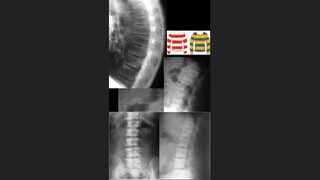

La valoración de la médula

La osteoradiología